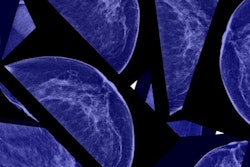

To overcome these obstacles, European researchers developed Mammi-PET, a high-resolution, full-ring PET device designed to create 3D images of the breast with no need for compression. The patient lies facedown with her breast hanging through an opening in the exam table. The system's field-of-view is approximately 19 cm.

With Mammi-PET, the patient hangs her breast through an opening in the exam table and into a sleeve to measure the length of the breast. All images courtesy of AJR.The original Mammi-PET prototype was developed in 2010, and subsequent research at the Mayo Clinic in Rochester, MN, found that the system had spatial resolution of around 1.6 mm, versus 5 mm to 6 mm for whole-body PET. It also requires only 2.5 mCi to 4 mCi of radiopharmaceutical, compared with 10 mCi to 15 mCi for whole-body PET.